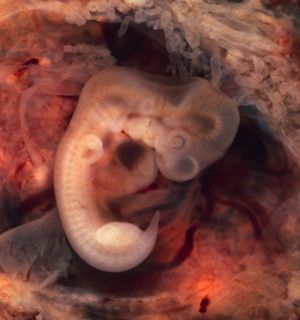

المضغة بالانجليزية Embryo ، باليونانية ἔμβρυον ، وهو طور من مراحل تطور الجنين في الإنسان ، ويكون في الفترة من بداية الإخصاب حتى نهاية الأسبوع الثامن من الحمل.

يأتي طور المضغة بعد مرحلتي النطفة و العلقة ، ويبدأ بظهور الكتل البدنية في اليوم الرابع والعشرين أو الخامس والعشرين في أعلى اللوح الجنيني ، ثم يتوالى ظهور هذه الكتل بالتدريج إلى مؤخرة الجنين. وفي اليوم الثامن والعشرين يتكون الجنين من عدة فلقات تظهر بينها انبعاجات ، مما يجعل شكل الجنين شبيهاً بالعلكة الممضوغة. ويزداد اكتساب الجنين في تطوره شكل المضغة تدريجياً من حيث الحجم بحيث يكتمل هذا الطور في بقية الأيام الأربعين الأولى من حياته ، وينتهي هذا الطور بنهاية الأسبوع السادس.

يحدث بعد ذلك تغير لأوضاع الجنين نتيجة تحولات في مركز ثقله مع تكون أنسجة جديدة ، ويشبه ذلك تغير وضع وشكل المادة حينما تلوكها الأسنان. وكما تستدير المادة الممضوغة قبل أن تبلع، فإن ظهر الجنين ينحنى ويصبح مقوساً شبه مستدير مثل حرف (C) بالإنجليزية. يكون طول الجنين حوالي 1 سم في نهاية هذه المرحلة ، لأن جميع أجهزة الإنسان تتخلق في مرحلة المضغة ولكن في صورة برعم ويكون طول الجنين في مرحلة المضغة ما يقارب 1 سم.

ويبدأ ظهور بعض الأعضاء ، كالعينين و اللسان وذلك في الأسبوع الرابع في مرحلة المضغة و الشفتين في الأسبوع الخامس ، ولكن لا تتضح المعالم إلاّ في نهاية الأسبوع الثامن. وتظهر نتوءات الأطراف اليدين و الساقين في هذا الطور. كذلك يمكن بسهولة تميز بروز القلب. ويعتبر الذيل المنحني باتجاه البطن وبما يحمله من الفلقات من الملامح المميزة لهذه المرحلة.